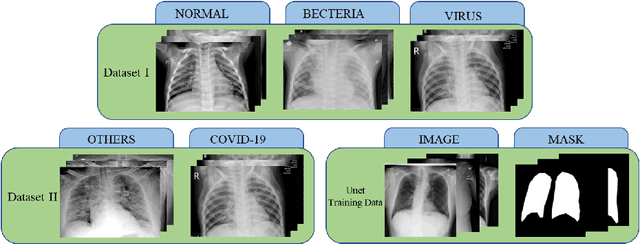

Abstract:The worldwide spread of pneumonia caused by a novel coronavirus poses an unprecedented challenge to the world's medical resources and prevention and control measures. Covid-19 attacks not only the lungs, making it difficult to breathe and life-threatening, but also the heart, kidneys, brain and other vital organs of the body, with possible sequela. At present, the detection of COVID-19 needs to be realized by the reverse transcription-polymerase Chain Reaction (RT-PCR). However, many countries are in the outbreak period of the epidemic, and the medical resources are very limited. They cannot provide sufficient numbers of gene sequence detection, and many patients may not be isolated and treated in time. Given this situation, we researched the analytical and diagnostic capabilities of deep learning on chest radiographs and proposed Cascade-SEMEnet which is cascaded with SEME-ResNet50 and SEME-DenseNet169. The two cascade networks of Cascade - SEMEnet both adopt large input sizes and SE-Structure and use MoEx and histogram equalization to enhance the data. We first used SEME-ResNet50 to screen chest X-ray and diagnosed three classes: normal, bacterial, and viral pneumonia. Then we used SEME-DenseNet169 for fine-grained classification of viral pneumonia and determined if it is caused by COVID-19. To exclude the influence of non-pathological features on the network, we preprocessed the data with U-Net during the training of SEME-DenseNet169. The results showed that our network achieved an accuracy of 85.6\% in determining the type of pneumonia infection and 97.1\% in the fine-grained classification of COVID-19. We used Grad-CAM to visualize the judgment based on the model and help doctors understand the chest radiograph while verifying the effectivene.